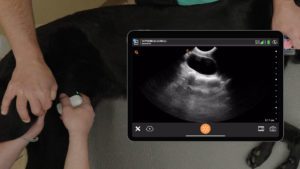

Not everyone wants to enter the market at a $30,000 price range before they even use ultrasound. So, I suggest that they enter the market using a Clarius,” he explains. “I get great resolution. I can see all the fillers I need to see, as well as the vascular structures.”

The Clarius L20 HD3 has become the ultrasound scanner of choice for many medical aesthetic practitioners looking to improve patient safety. It’s the world’s only ultra-high frequency ultrasound in a wireless scanner that shows the fine detail required to clearly image the skin, muscles, fascia, and vessels of the face. Visit our Facial Aesthetics page to learn more.